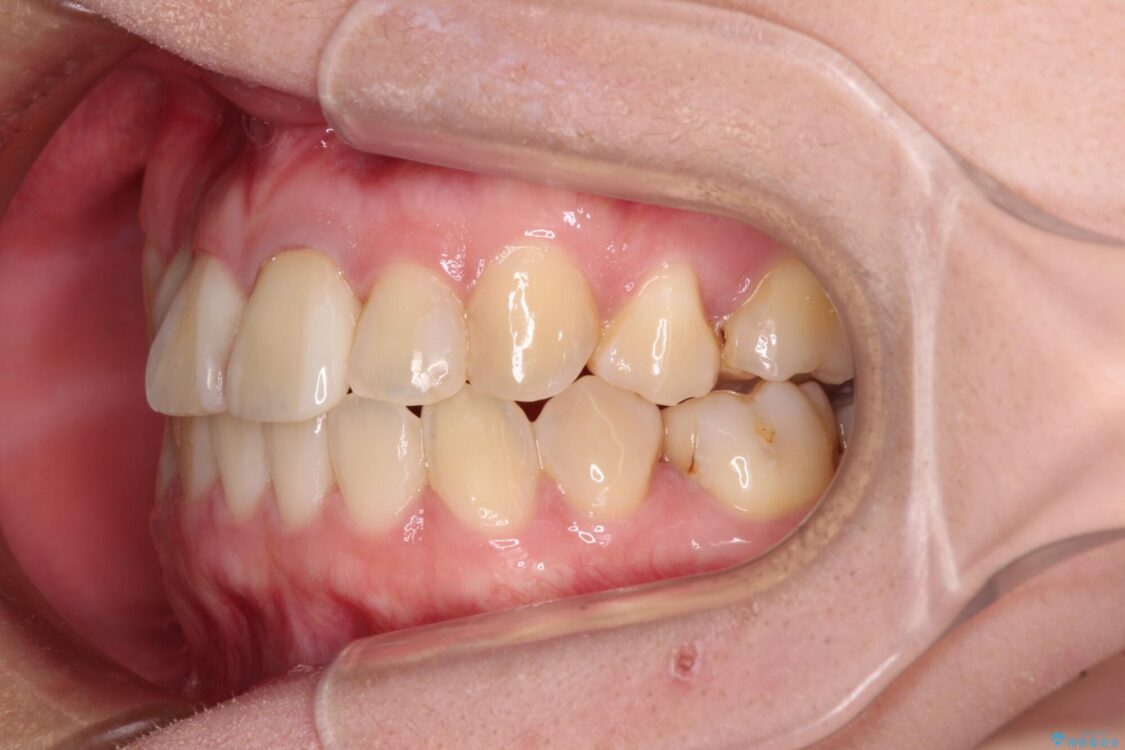

治療前

• 虫歯治療ついでに歯並びの後戻りを改善 インビザラインによる矯正治療 治療前画像